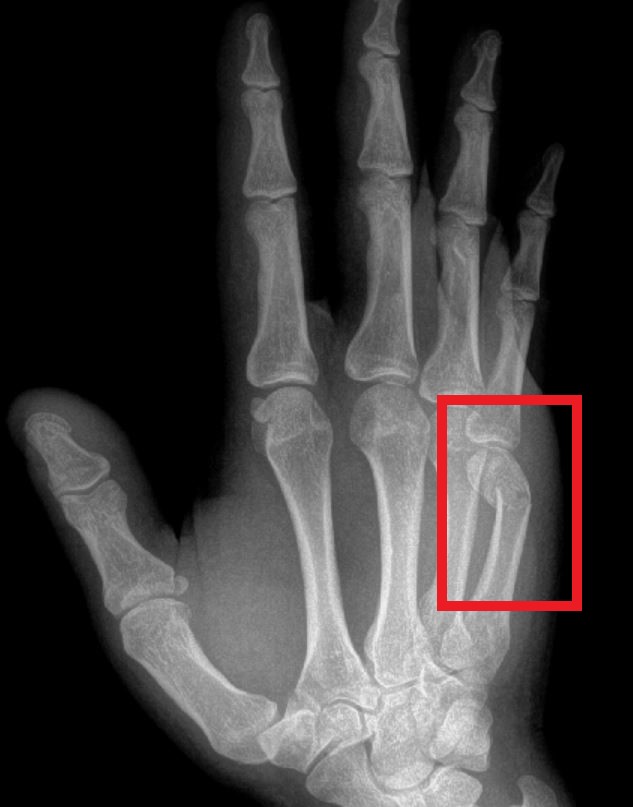

- Beeldvorming: Een röntgenfoto van de hand wordt gemaakt om de breuk te bevestigen en details te zien. Op de röntgenfoto is duidelijk zichtbaar welk middenhandsbeentje gebroken is en of de botdelen verplaatst zijn. Soms zijn er meerdere breuken. In de regel volstaat een gewone röntgenfoto. Bij zeer complexe letsels of als er mogelijk schade aan gewrichten is, wordt een aanvullende CT-scan gedaan.

Een boksersfractuur is een breuk van het vijfde middenhandsbeentje, net onder de pink. Dit is een specifiek type metacarpaal fractuur – zo noemen we elke breuk van één van de vijf middenhandsbeentjes in de handpalm. Een boksersfractuur ontstaat klassiek door een vuistslag tegen een hard voorwerp (bijvoorbeeld een muur of tijdens een gevecht). Hierbij breekt meestal de kop van het botje onder de pink. De knokkel van de pink ziet er daardoor ingezakt uit en je kunt soms een voelbare inkeping op de handrug merken.